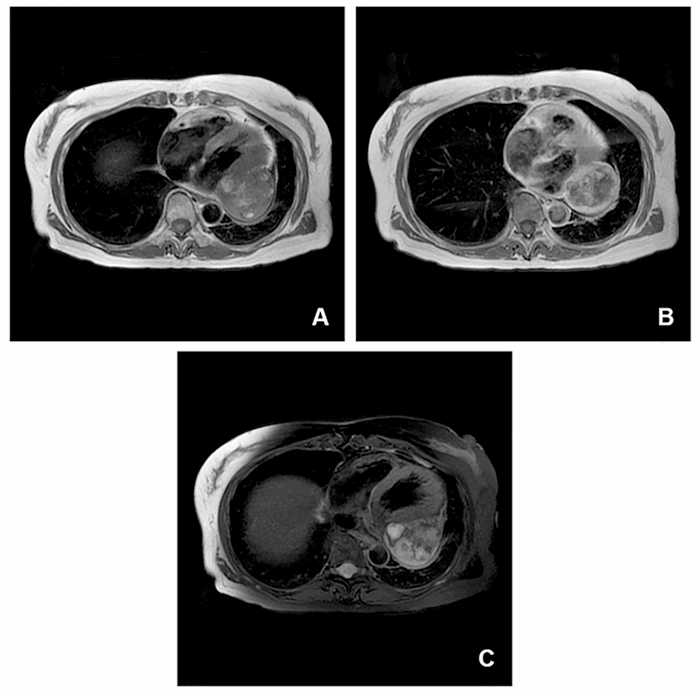

A 70-year-old female without significant co-morbidities presented to the emergency room after being involved as a restrained passenger in a high-speed motor vehicle crash. Because of the high-energy mechanism and complaints of anterior chest pain, the patient underwent CT of the chest. In addition to a minimally displaced fracture of the upper sternal body, imaging identified a 4.7 cm × 5.9 cm × 8.1 cm soft tissue mass adjacent to the left atrioventricular groove and circumflex coronary artery (Figure 1).

Figure 1. Axial and Coronal Cuts of a Thoracic CT Scan with Trauma-Protocol IV Contrast Demonstrate a Heterogeneous Left-Sided Mediastinal Tumor with Unclear Anatomical Association. Published with Permission

There were no suggestions that this incidental lesion was associated with the traumatic event. The patient was discharged from the hospital the following day, and an outpatient workup of the cardiac mass was recommended. The patient underwent a transthoracic echocardiogram demonstrating normal biventricular function and no valvular dysfunction, followed by a gated cardiac MRI and PET-CT (Figure 2).

Figure 2. Axial T1 Double IR. Published with Permission

A) +C T1 Double IR; B) T2 Double IR FS; C) Cuts of a thoracic MRI demonstrating heterogeneous nature of mediastinal mass as well as its close association with left atrioventricular groove

This additional imaging showed a large mass in the posterolateral AV groove inseparable from the myocardium, immediately inferior to the atrial appendage with associated distortion of the left inferior pulmonary vein. The mass was heterogeneous on T2 weighted post-gadolinium imaging and on PET and was therefore considered suspicious for sarcoma. The PET was otherwise negative for regional or distant disease. A CT-guided core needle biopsy was acellular and demonstrated only densely packed fibrin.